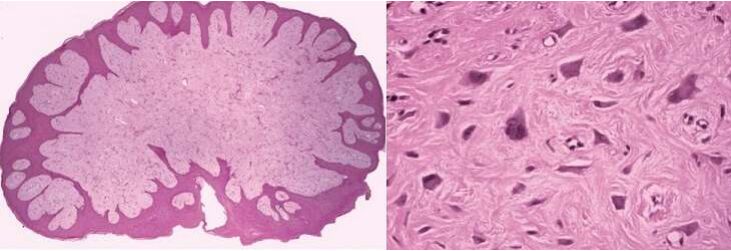

1.下圖是那一種囊腫的組織切片影像? (A)甲狀腺舌管囊腫(thyroglossal duct cyst) (B)表皮樣囊腫(epidermoid cyst) (C)淋巴上皮囊腫(lymphoepithelial cyst) (D)鼻腭管囊腫(nasopalatine duct cyst)

6.在高倍鏡下有如附圖之發現,依此推斷該病灶發生的部位,下列何者可能性最高? (A)下顎臼齒區域(lower molar area)(B)上顎前牙區域(upper anterior area)(C)副鼻竇(paranasal sinus) (D)頰黏膜(buccal mucosa)